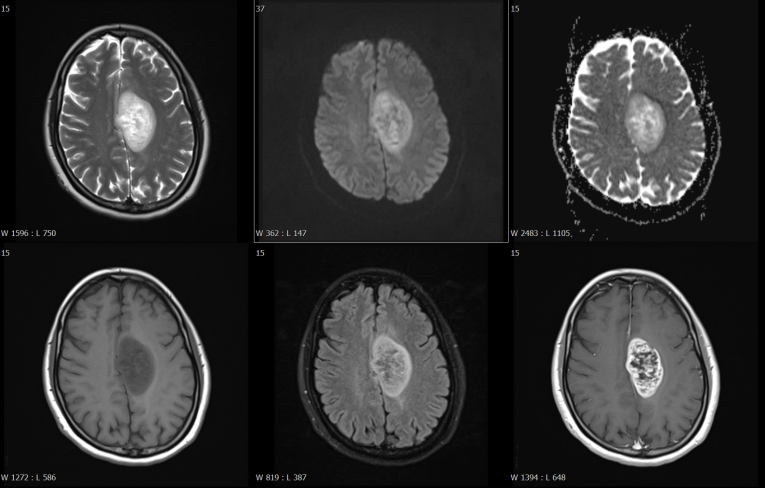

磁共振檢查方面,開展了高技術(shù)的增強(qiáng)掃描動態(tài)分析,動態(tài)灌注掃描、波譜分析,為腫瘤鑒別提供了有效方法,比如腦內(nèi)膠質(zhì)瘤、淋巴瘤的鑒別。

乏血供病變---淋巴瘤